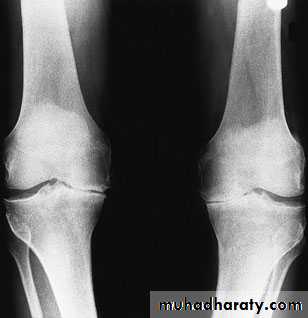

Radiographic features of OA

1- Asymmetric loss of cartilage ( narrowing of joint space).2-Sclerosis of subchondral bone, with subchondral cyst sometimes.

3- Osteophytes (spurring of the joint margins directed toward joint line).